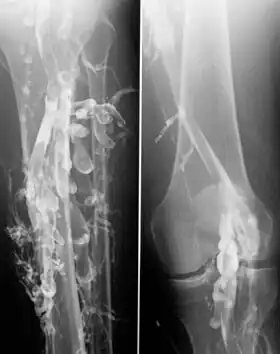

![]() Venography in a patient with deep vein thrombosis | |

Venography (also called phlebography or ascending phlebography) is a procedure in which an X-ray of the veins, a venogram, is taken after a special dye is injected into the bone marrow or veins. The dye has to be injected constantly via a catheter, making it an invasive procedure. Normally the catheter is inserted by the groin and moved to the appropriate site by navigating through the vascular system.

Contrast venography is the gold standard for judging diagnostic imaging methods for deep vein thrombosis; although, because of its cost, invasiveness, and other limitations, this test is rarely performed.[1]